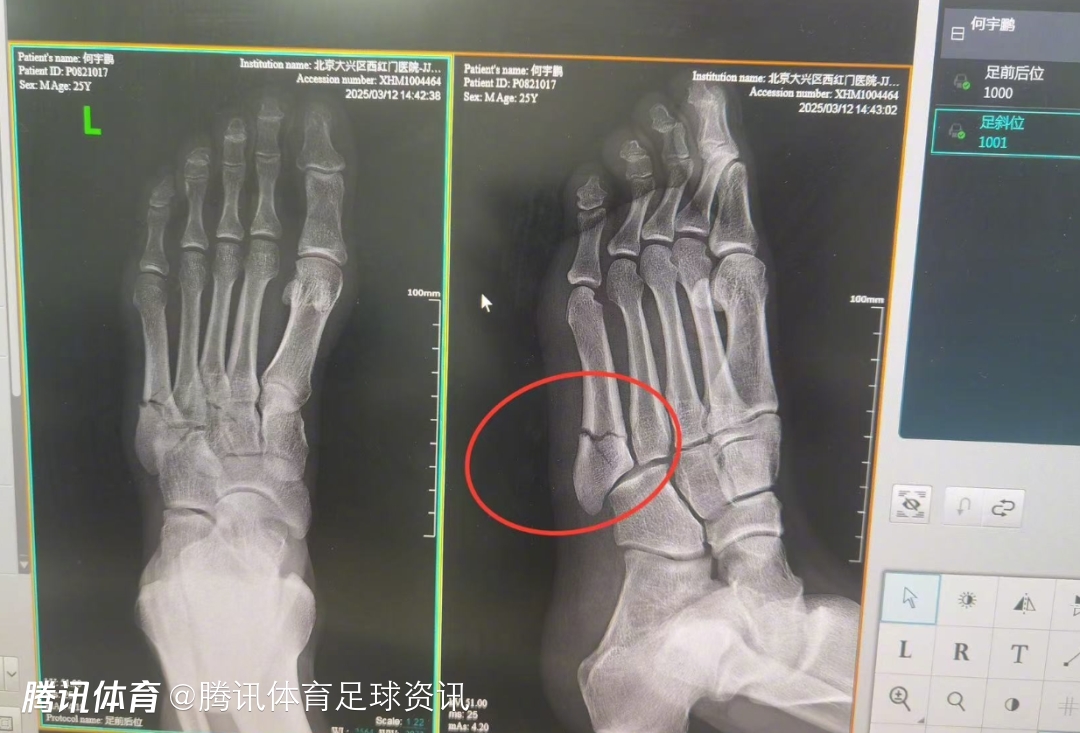

遭遇重伤!官方:国安后卫何宇鹏左足第五跖骨基底部粉碎性骨折

2025-03-13 20:00北京时间3月13日,北京国安官方通报了球员何宇鹏的伤情,他被诊断为左足第五跖骨基底部粉碎性骨折。

2025年3月12日,队内有球对抗训练时,何宇鹏不慎扭伤左足,当即感到左足外侧剧烈疼痛。队医立即紧急处理,判断为左足第五跖骨骨折可能,并立即冷敷加压特殊处理后,去医院进行影像检查。

经左足X光片提示,诊断结果为:左足第五跖骨基底部粉碎性骨折。